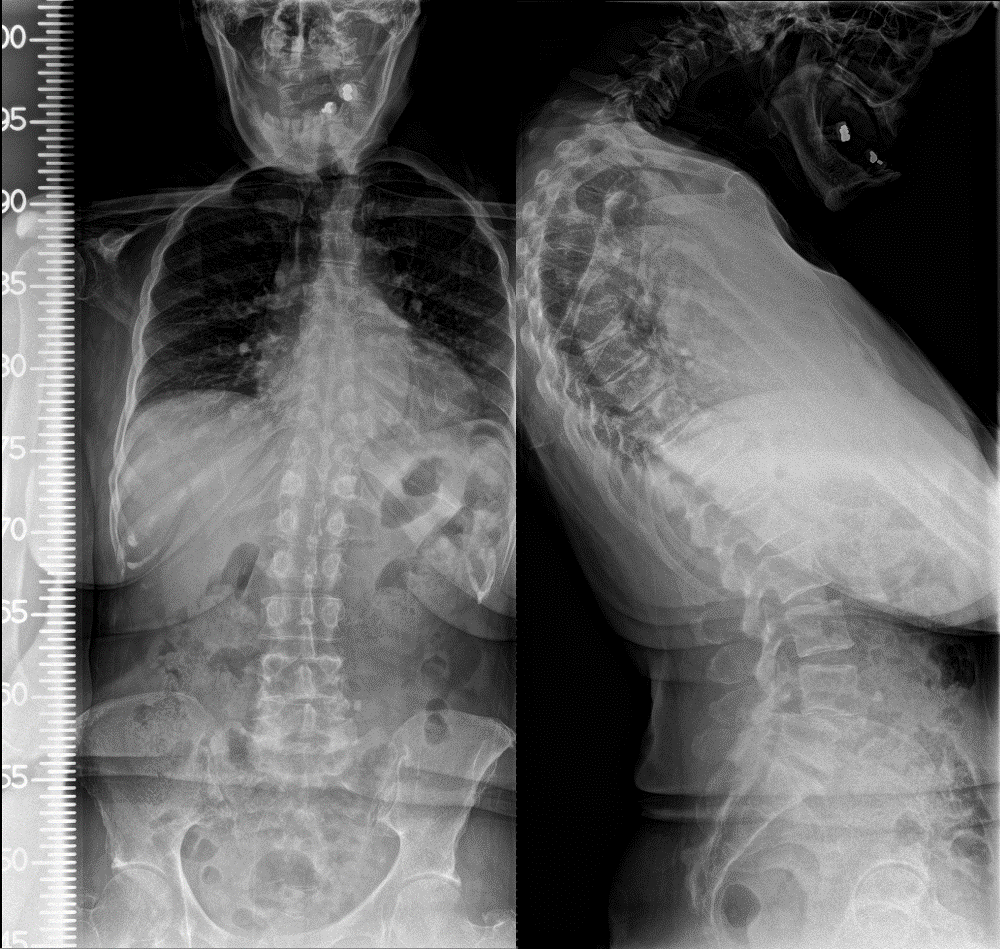

Chest wall deformity on left. Download Scientific Diagram

Chest Xray show fixed scoliotic deformity. The major scoliosis is What Is Chest Deformity Chest wall deformities occur when the cartilage. Surgery helps correct the deformity. This article deals with two of the three most common chest deformities: Some people call it “pigeon chest” or “keel. These can manifest as isolated conditions or can correlate. Surgery helps correct the deformity. Pectus excavatum (pe), translated literally as “hollowed chest” and also referred to as sunken. What Is Chest Deformity.